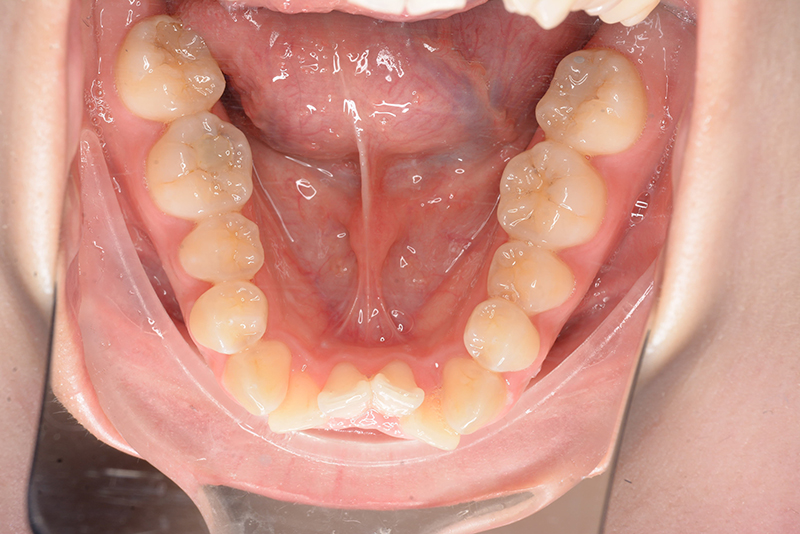

| 口腔内所見 | over jet 4.5mm、over bite 4.0mm、大臼歯関係 I級で上下顎前歯部に叢生が認められた。 |